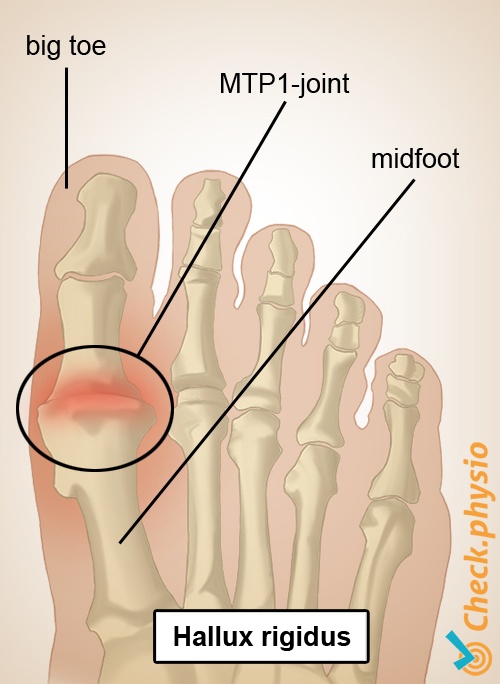

무지강직증은 무지외반증과는 다른 질환이다.

무지강직증은 엄지발가락의 Metatarsophalangeal joint(MP joint)에 생기는 퇴행성 관절염으로 관절에 염증 및 변형이 생겨 통증 및 강직을 주증상으로 하는 질환입니다.

엄지발가락의 MP joint가 2번째 발가락 쪽으로 꺾여서 비정상적인 각도를 이루어 통증 및 불편감을 유발하는 질환인 무지외반증과 그 형태가 비슷해 헷갈리기 쉬우며, 실제 엄지질환중 가장 많은 질환 중 하나로 여겨집니다.

무지강직증의 가장 흔한 증상은 엄지발가락 부위 통증 과 강직입니다.

초기에는 통증과 강직으로 인해 스쿼트나, 달리기 같은 활동이 어려워지고, 관절부위가 붓고 빨갛게 달아오르기도 합니다.

무지강직증이 만성화되면 만성적인 은은한 통증과 더불어, 골극(뼈조각)이 생겨 엄지발가락을 굽히고 펴는데 제한이 더 심해집니다. 또한 발의 통증이 아래다리, 무릎, 고관절, 허리에 영향을 미쳐서 무릎, 다리, 허리의 둔한 통증을 일으키고, 다리를 절뚝거리며 걷게 됩니다.

또한 무지강직증 환자는 보행시 toe off phase 단계에 엄지발가락 신전시 통증이 생기기 때문에 발을 외측으로 해서 보행하려는 경향을 보이고, 골극으로 인해 꽉조이는 신발을 신을 경우 자극이 되어 통증이 더 심해집니다.